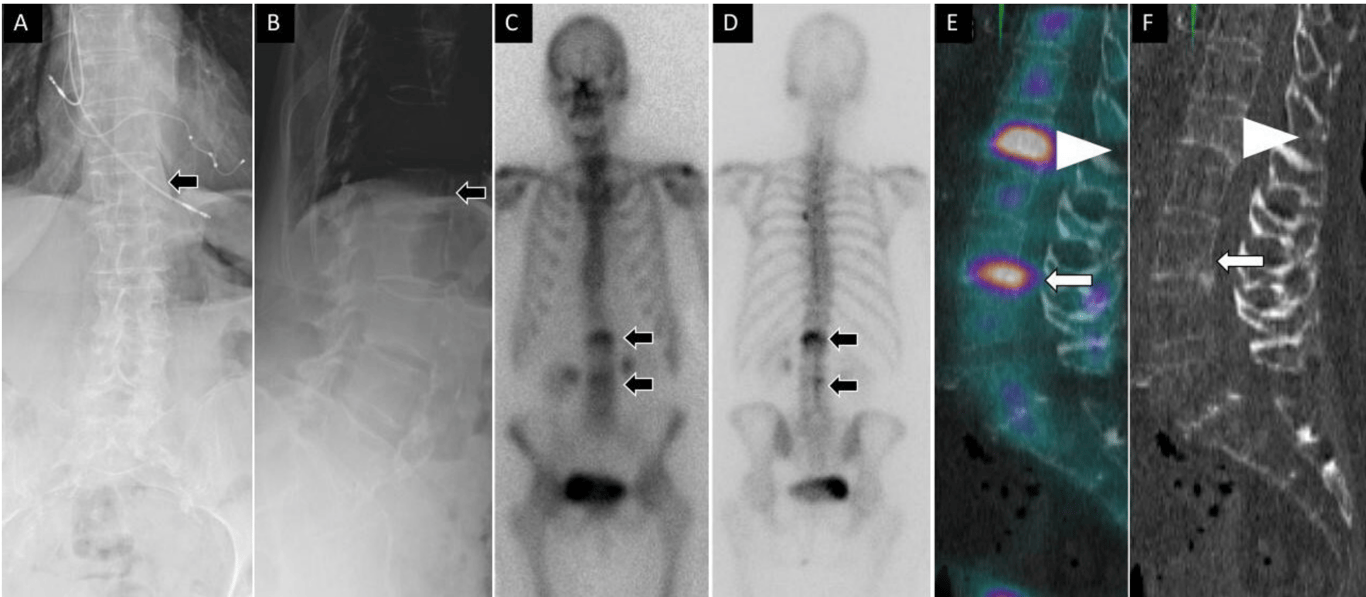

A 56-year-old woman presented with low back pain after prior L4 to S1 posterior instrumented fusion and subsequent standalone L3 to L4 anterior lumbar interbody fusion with anterior plate fixation. Lateral lumbar spine radiograph (A) shows fractured screw related to anterior instrumentation at the level of L4 (arrow). Sagittal T2 magnetic resonance imaging (B) shows no evidence of acute central canal stenosis and metal artifact (arrow) related to instrumentation. Sagittal noncontrast computed tomography (C) demonstrates fractured screw into the L4 vertebral body and sclerotic changes within the bone. Fused sagittal and coronal images demonstrate increased osteoblastic activity and radiotracer uptake within the L3 to L4 disc space concerning for hardware loosening and pseudoarthrosis